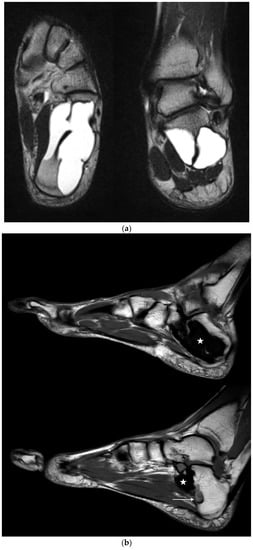

The mean follow-up (f/u) of 24/25 patients was 24.5 months (range 12–91). One patient (case 21) was lost to f/u after the first control six weeks postop. Patients showing complete osseous healing without any defect (Neer type A) in conventional X-rays and no symptoms one year postop were not required to undergo further imaging controls by our clinic, but were contacted by phone and/or mail in January 2021 asking for any additional imaging that was performed in the meantime. A return postage-paid envelope was mailed to the patients requesting the additional imaging. In two cases, the imaging was transmitted digitally. As a result, five more MRI follow-ups of were acquired for the initial Neer type A cases. Only one case (case 6) with MRI performed 91 months after index surgery showed small areas of recurrent SBC (Figure 6a,b), corresponding to a Neer type B healing. In the four remaining cases of initial type A healing, MRI with a mean f/u of 51.2 months (range 36–60) confirmed a complete healing.

Figure 6.

(a) Axial and coronal T2 TSE-weighted MRI showing a large SBC in a 31-year-old professional ballet dancer (case 6). After endoscopic resection, the bone cavity was filled with injectable bone substitute. (b) Sagittal T1-weighted MRI performed 91 months postop, showing two small areas of recurrence of SBC at the medial aspect (bottom image, arrows). The large cyst cavity was filled with QuickSet© injectable bone substitute (marked with a star), showing no signs of osseous remodeling more than 7.5 years after implantation. The patient is currently free of symptoms and still performs at the highest level of professional ballet dancing.

Figure 8.

Preoperative MRI of case 12 (19-year-old male patient) showing a calcaneal IOL with cystic changes corresponding to a Milgram Stage 3 type []. However, histopathological examination of the tissue samples taken from the bone cavity revealed SBC.